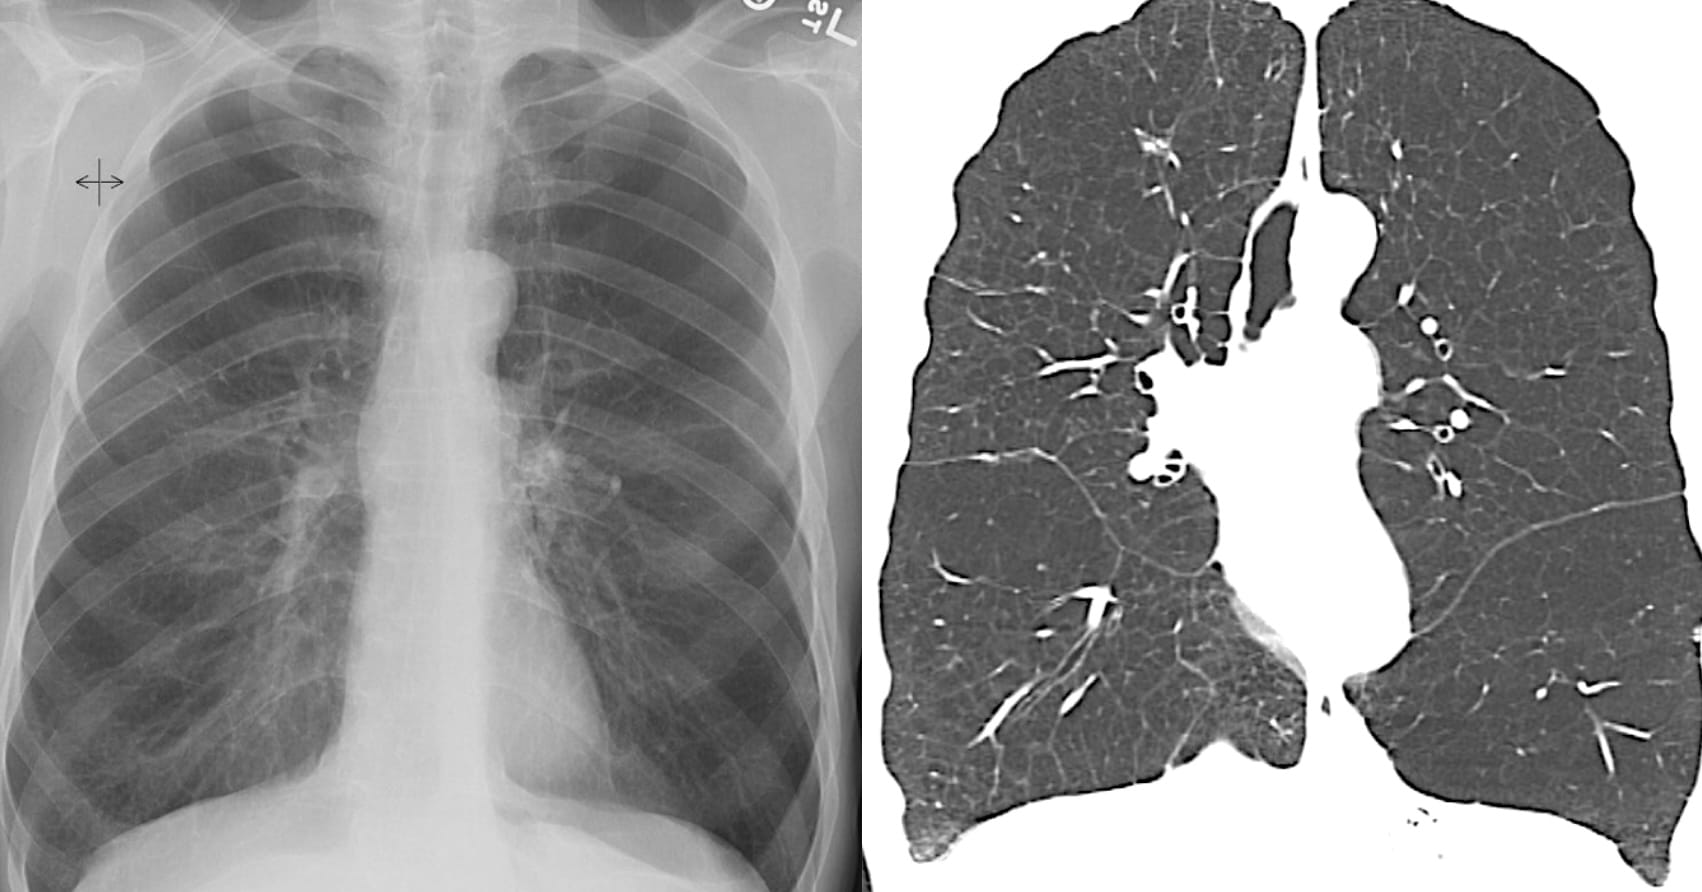

From the article:

“The cysts’ diameters in AEF are significantly larger than those in UIP and NSIP, but, at the same time, the walls are significantly thinner than those of UIP and thicker than those of centrilobular emphysema (CLE)”

Examples from the article:

One observation seems relevant: the cystic spaces may be situated away from the pleural surface.